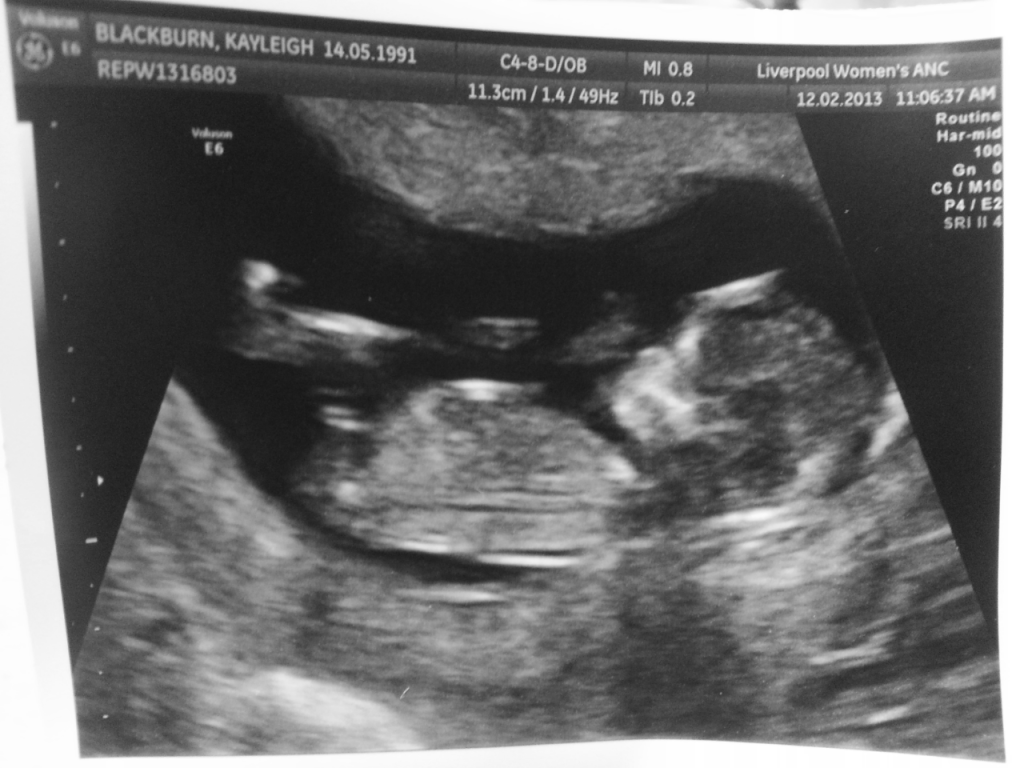

Nub theory 12 weeks 4 day scan — The Bump

From www.mumsnet.com

From community.babycentre.co.uk

From www.netmums.com